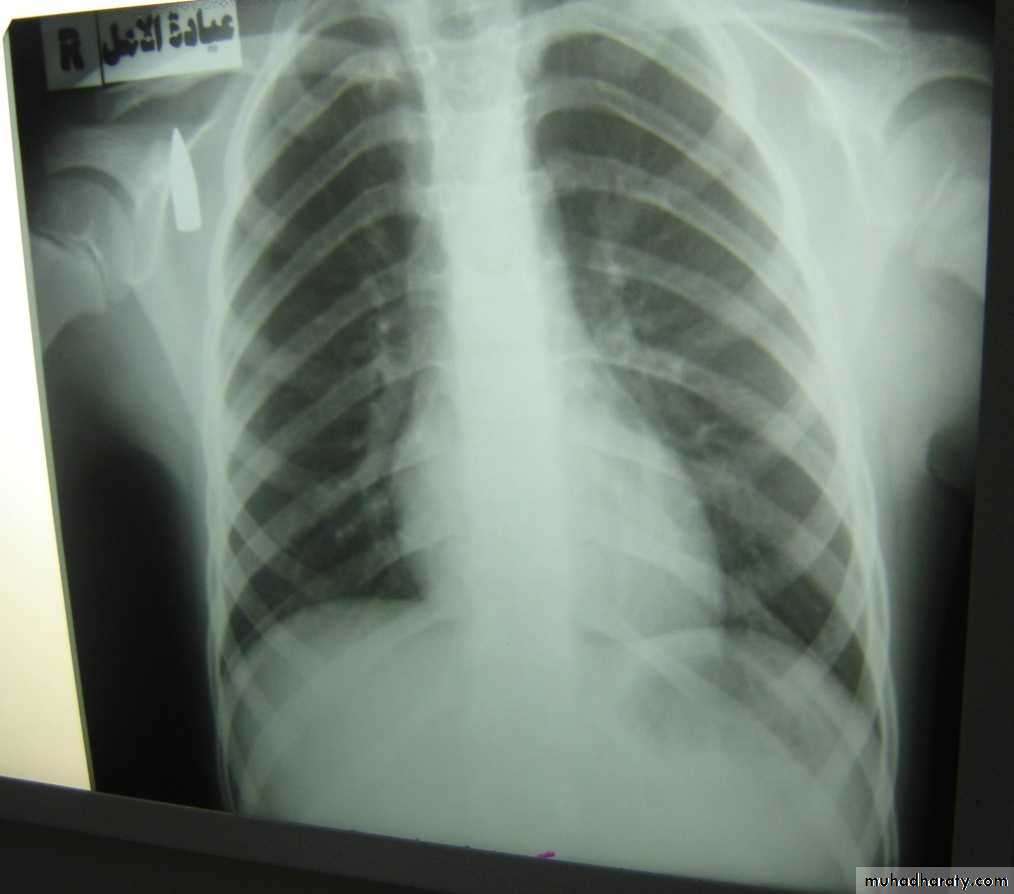

• Radio logically (concave meniscus sign)

• A-Asymptomatic• Any smooth homogenous opacity of uniform density with clear cut border and little or no reaction around it on a chest X-Ray is a hydatid cyst unless proved the other wise .